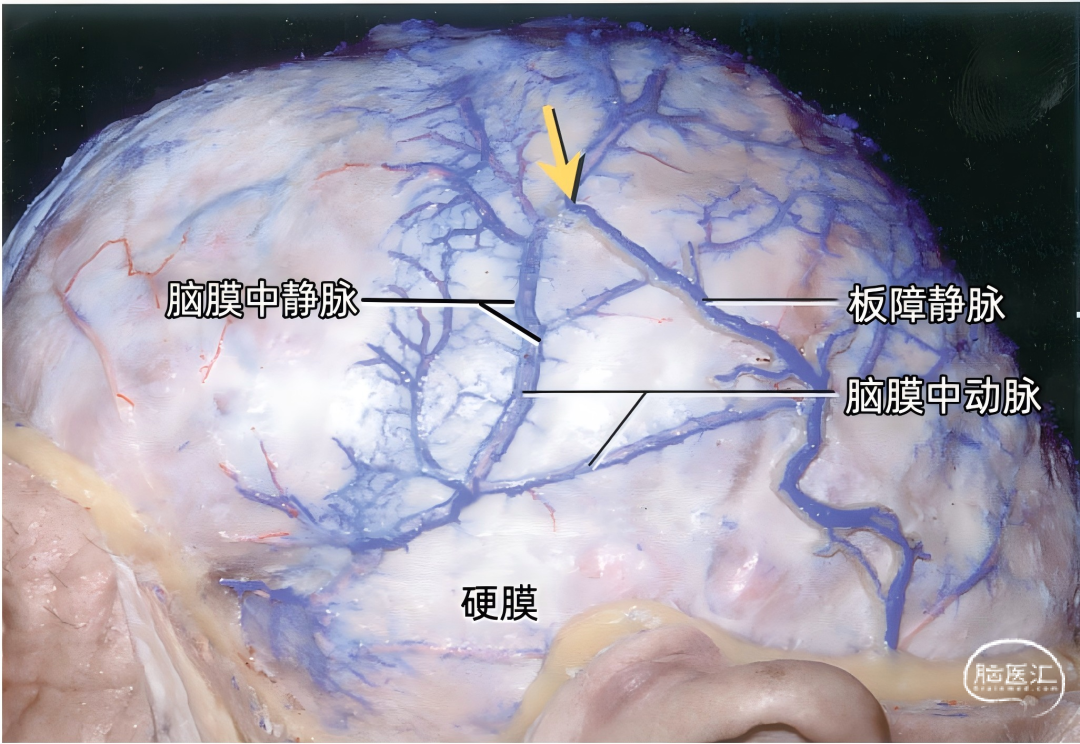

▼3.脑膜静脉

引流硬膜血液的小静脉通道称为脑膜静脉。它们其实是小静脉窦。脑膜静脉多数与脑膜动脉伴行,一般是每一条动脉有一条伴行静脉,但脑膜中动脉有两条伴行静脉。与脑膜动脉伴行的脑膜静脉走行在动脉与骨板之间,实际上伴行的动脉嵌入静脉内,看起来是平行的静脉管腔位于动脉的两侧。 有的脑膜静脉可能在颅骨内板的浅沟内走行,有板障内和硬膜内两个行程,使得颅骨骨折时尤其易于被撕裂。 硬脑膜的动脉和静脉之间存在着丰富的血管吻合。动脉与静脉常常并列行进,而且存在着50~90μm的动、静脉交通,以在静脉窦附近多见,在临床上容易形成硬脑膜动-静脉瘘。 脑膜静脉末段管腔扩大不明显,主要汇入附近的硬脑膜窦,特别是上矢状窦两侧的外侧陷窝。在大脑的上缘,进入静脉腔隙或上矢状窦。在大脑的下缘,脑膜静脉进入颅底的大静脉窦。 脑膜中静脉属支通过上矢状窦的静脉腔隙与上矢状窦相交通。这些属支在下方彼此汇聚并融合成额干、顶干。脑膜中静脉额干伴行于脑膜中动脉前支经卵圆孔达翼静脉丛或者进入蝶顶窦、海绵窦或蝶骨导静脉;脑膜中静脉顶干伴行于脑膜中动脉后支可经棘孔与翼静脉丛交通。

脑膜中静脉接纳脑膜支和小的大脑下静脉,并与板障静脉、大脑中浅静脉也有广泛的交通。蛛网膜粒也经常投射其中。

脑膜静脉接受板障的静脉回流。板障静脉(上图)被认为是构成静脉的第四种层次。然而,由于其引流注入脑膜静脉,所以将其归为脑膜静脉系统。值得提出的是颅内静脉在许多部位通过导静脉或其他静脉与颅外血管相交通。上图示切除颅骨外板,保留骨缝,暴露穿行于内、外板之间的板障静脉。 下图示切除颅骨内板,最大的脑膜中静脉与脑膜中动脉伴行。我们保留后组较大的板障静脉,可见此板障静脉上端连接围绕脑膜中动脉的静脉窦(由黄色箭头显示)。

下图示覆盖在大脑半球表面的硬膜,包含有沿脑膜中动脉分支分布的小硬膜窦的丛。最大的硬膜窦沿着脑膜中动脉前、后分支分布,向上进入上矢状窦或其附近的静脉腔隙。